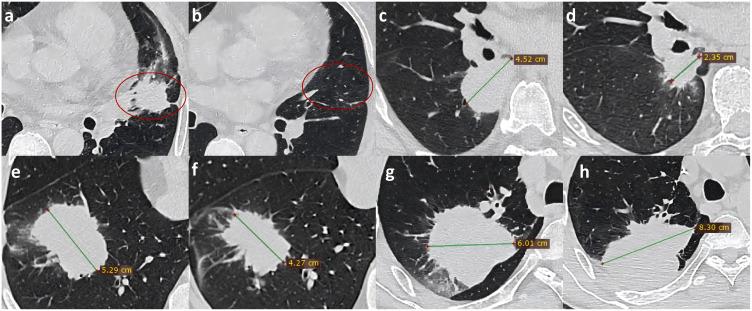

Immunotherapy has emerged as a transformative treatment for non-small cell lung cancer (NSCLC), yet its clinical benefits remain variable among patients. Early and accurate evaluation of treatment response is critical to guide therapeutic adjustments and improve outcomes. This review synthesizes recent advancements in multimodal imaging techniques-computed tomography (CT), positron emission tomography (PET)/CT, magnetic resonance imaging (MRI), and radiomics-for evaluating and predicting immunotherapy efficacy in NSCLC. We analyze the strengths and limitations of conventional morphological criteria (eg, RECIST, iRECIST) and highlight emerging quantitative biomarkers, including CT texture analysis, metabolic parameters (MTV, TLG), and diffusion-weighted MRI metrics. Notably, radiomics demonstrates promise in decoding tumor heterogeneity, PD-L1 expression, and immune microenvironment features, while immuno-PET probes targeting immune checkpoints offer novel insights into immune activity in vivo. Challenges such as pseudo-progression, nodal immune flare, and discrepancies between imaging responses and pathological responses are critically discussed. By integrating morphological, metabolic, and microenvironmental data, multimodal imaging enhances precision in patient stratification and therapeutic monitoring. Future research should prioritize multicenter, AI-driven radiomics validation and targeted tracer development to optimize NSCLC immunotherapy management. This review provides clinicians and researchers with new directions for utilizing multimodal imaging techniques in developing personalized treatment strategies.